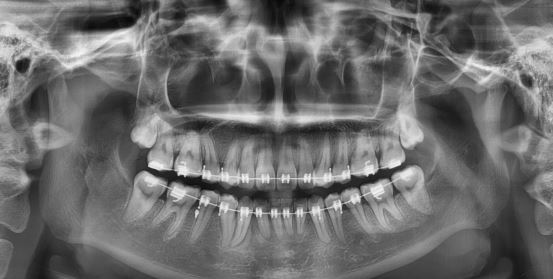

마무리단계

마무리 해도 될거 같다고 하시는데요. 윗니가 아랫니 덮는 정도가 적당한건지 궁금해요. 그리고 아래앞니 두개가 높이가 안맞는데 교정 가능한건가요??